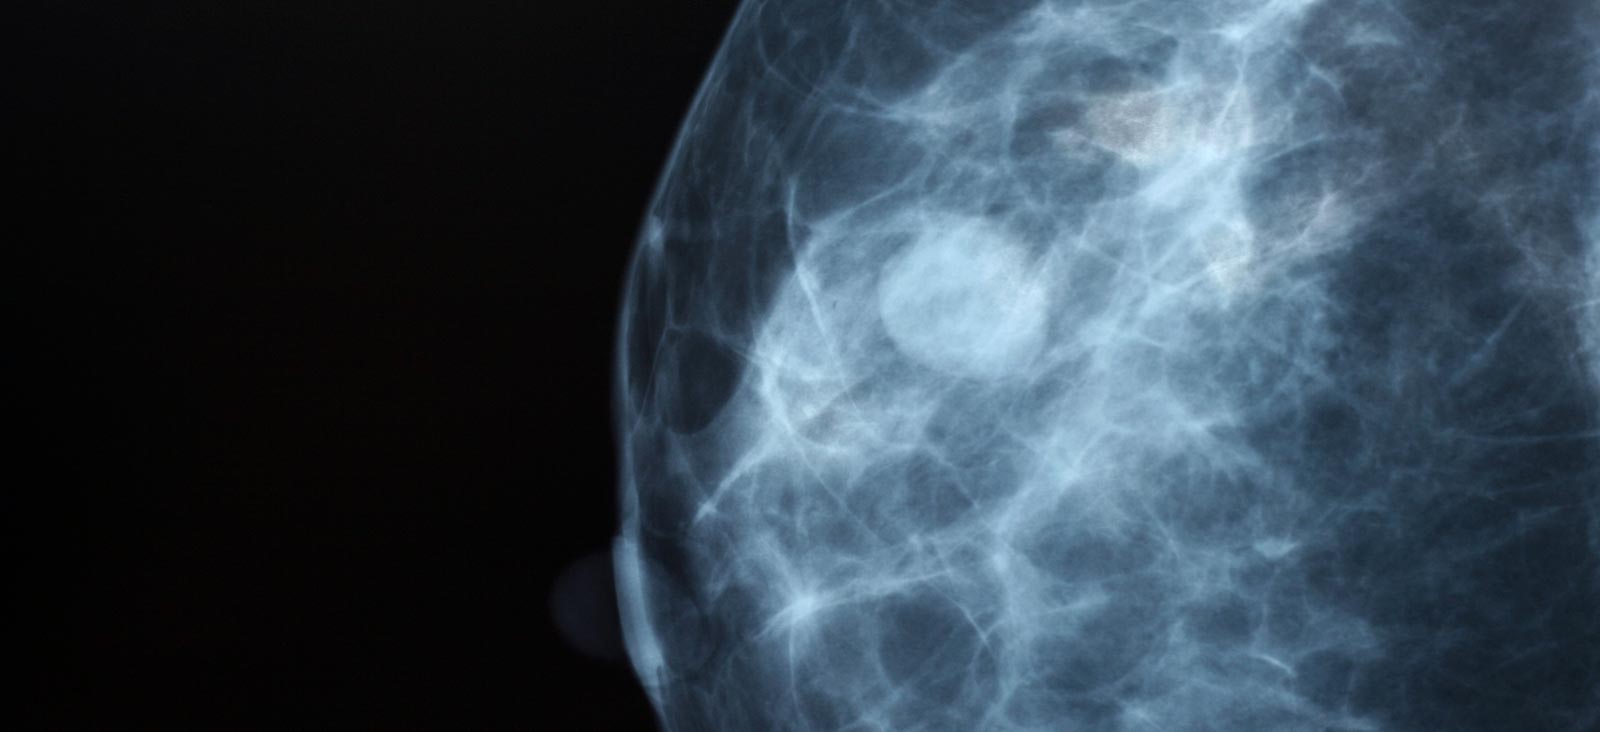

Breasts contain three main types of tissue: glandular, fibrous connective, and fatty tissues. Fatty tissue appears dark on a mammogram, while glandular and fibrous connective tissues appear white. The problem is that tumors also appear white, making it difficult to identify what is normal breast tissue and what may be cancer.

Dense breasts have higher amounts of glandular and fibrous connective tissues and lower amounts of fatty tissue. Breast density is classified into four categories using the American College of Radiology BI-RADS system:

A standard mammogram and 3D mammogram (tomosynthesis) both use a low-dose X-ray to produce an image of the breast. Unfortunately, the sensitivity of a mammogram can go down to as low as 25% to 30% for dense breasts as compared to almost 100% sensitivity for fatty breasts.

Mammograms are still valuable for women with dense breasts. Even with dense breasts, we can still detect ductal carcinoma in situ (DCIS), a very early form of breast cancer, with a mammogram. This is because it is a calcification and not a soft tissue tumor. Because of this, I would never say a mammogram is worthless, despite the density of your breasts.